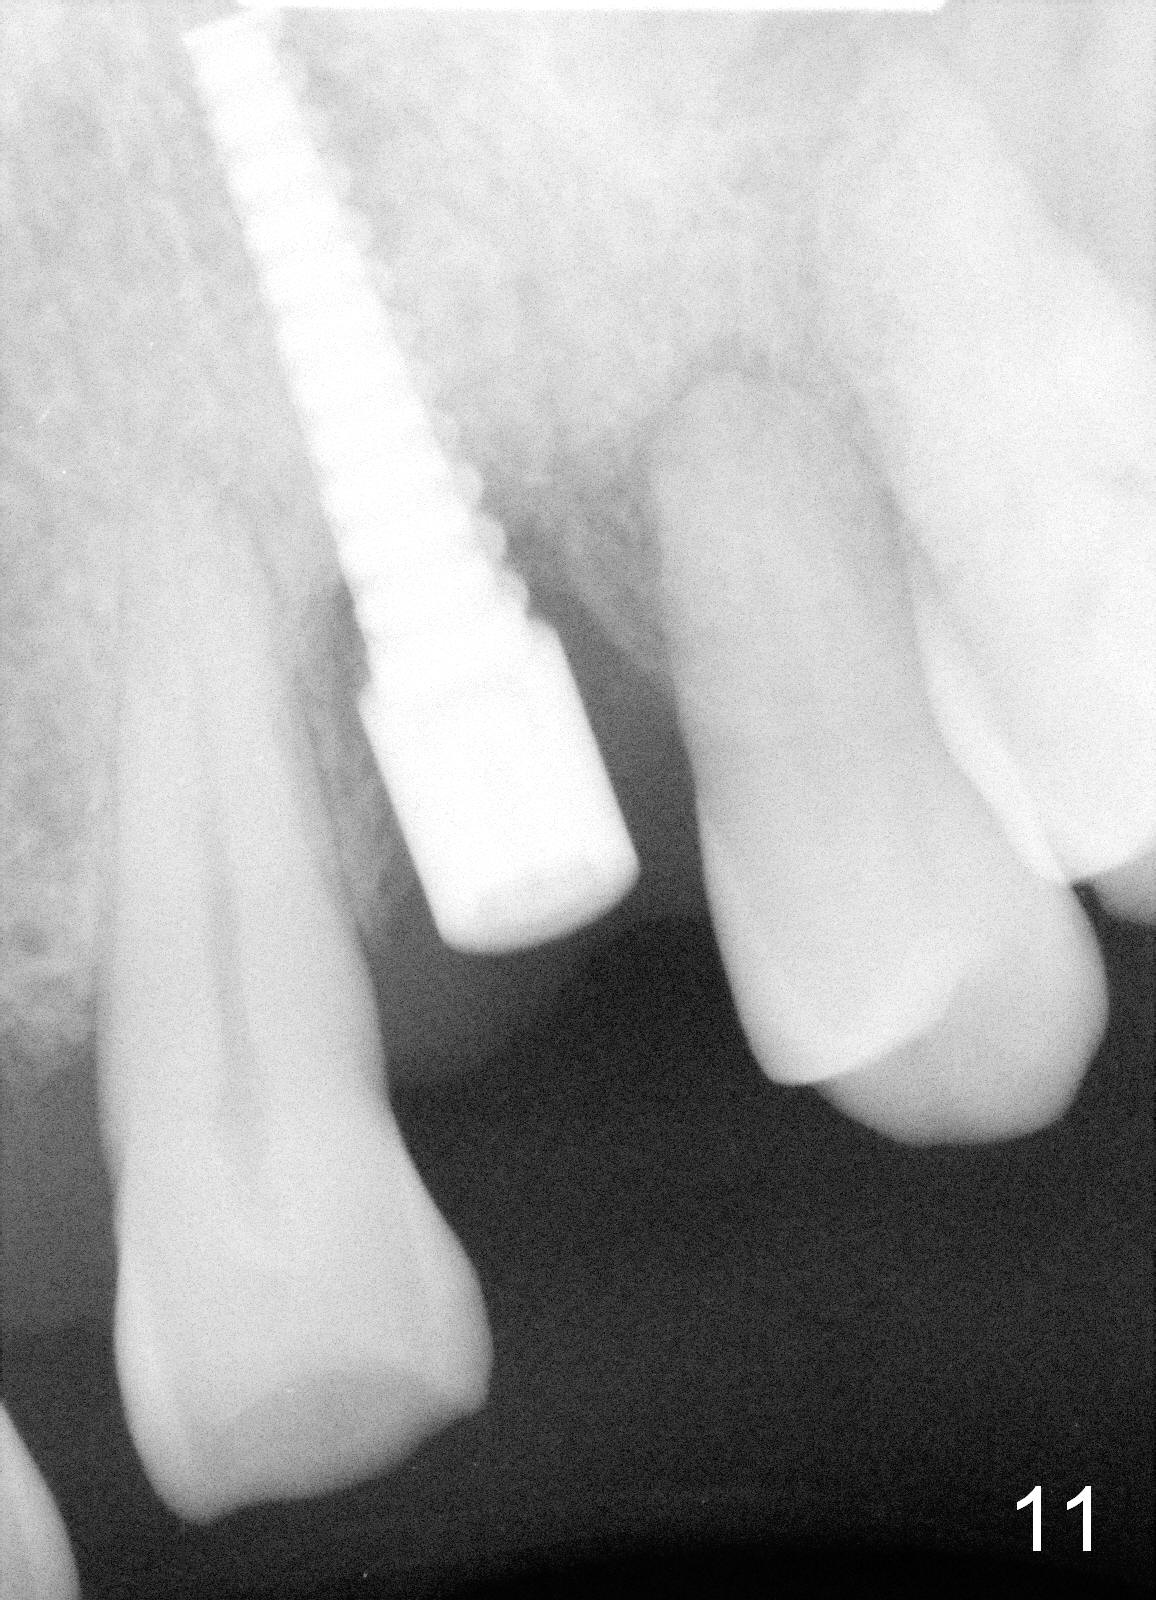

Dear Drs. Dunson and Borgner: Thank you for support. Fig.5 and 6 taken immediately prior to surgery show that the healing socket is elliptical (arrowhead). After D1 and D2 channel formers, D2 thin socket former is tapped in (Fig.7). The osteotomy needs to be redirected as shown by the black line. D2 implant is being inserted with Synthograft applied to the 1st two threads (Fig.8) and is in place (Fig.9,10). But the implant is not as stable as expected. There is a gap mesial to the implant (Fig.10 arrowhead), which is most likely created by re-directing the osteotomy with channel and socket formers.